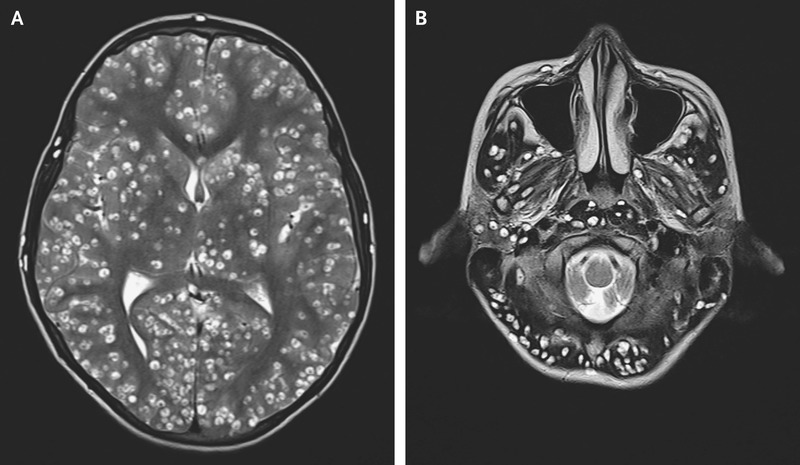

Диссеминированный церебральный нейцистицеркоз. 18-летний мужчина поступил в отделение неотложной помощи с генерализованными тонико-клоническими судорогами. МРТ головы показала многочисленные четко выраженные кистозные поражения в головном мозге, которые соответствовали цистицеркозу. Nishanth Dev, M.D., and S. Zafar Abbas, M.D. Disseminated Cysticercosis. N Engl J Med 2019; 380:1267 DOI: 10.1056/NEJMicm1810953

Различие между паренхиматозным и экстрапаренхиматозным нейроцистицеркозом имеет важное прогностическое значение. Паренхиматозная болезнь с небольшим количеством цист (менее 50) имеет хороший долгосрочный прогноз, возможно, даже без антигельминтной терапии, в то время как паренхиматозная болезнь с более чем 50 цистами или экстрапаренхиматозная болезнь имеют менее благоприятный прогноз.